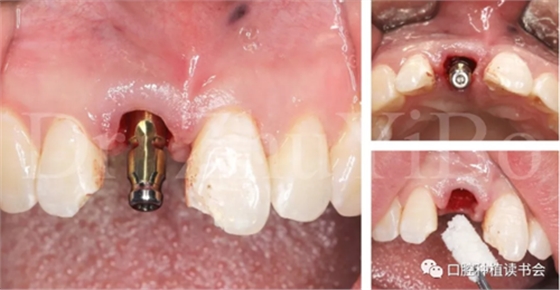

臨床檢查發(fā)現(xiàn):右上中切牙冠根折,斷面位于齦緣下4到5個(gè)毫米。左上中切牙及右上側(cè)切牙,切角缺損,牙髓活力正常(圖7)。

術(shù)前cbct顯示:右上中切牙牙根牙槽突類型為一型(圖8)。牙齦為厚型牙齦類型;咬合關(guān)系基本正常。

圖7 外傷導(dǎo)致11冠根折

圖8 CBCT:11可見明顯根折線,無法保留

4.2.1微創(chuàng)拔出牙齒,挺出根尖(圖9)

4.2.2 拔牙窩沖洗,定點(diǎn),備洞(圖10)。

4.2.3 植入Nobel active種植系統(tǒng) RP 13mm種植體,植入扭矩大于45Ncm,初期穩(wěn)定性良好(圖11、圖12))。

圖12 種植體初期穩(wěn)定性良好,注意與唇側(cè)骨板間的間隙

4.2.4取模,制作臨時(shí)修復(fù)體(圖13)。

4.2.5 雙區(qū)植骨,戴牙(圖14,圖15)。

圖16 即刻修復(fù)后,患者恢復(fù)了美觀